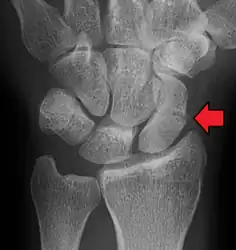

Radiolucency around a 12 days old scaphoid fracture that was initially barely visible.[11]